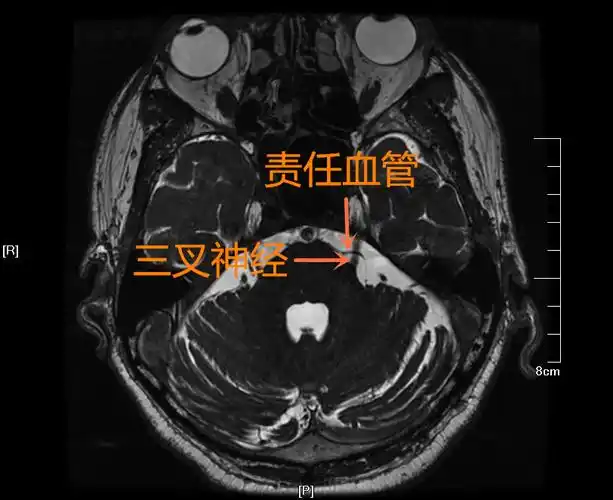

三叉神经解剖及mr表现

三叉神经痛?核磁共振放大招揪出元凶!